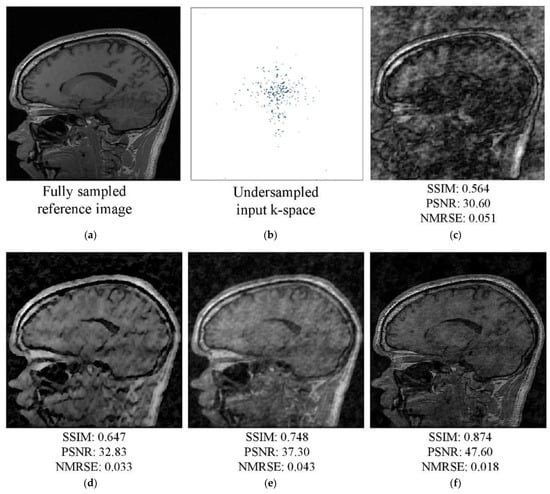

5. Results and Discussion